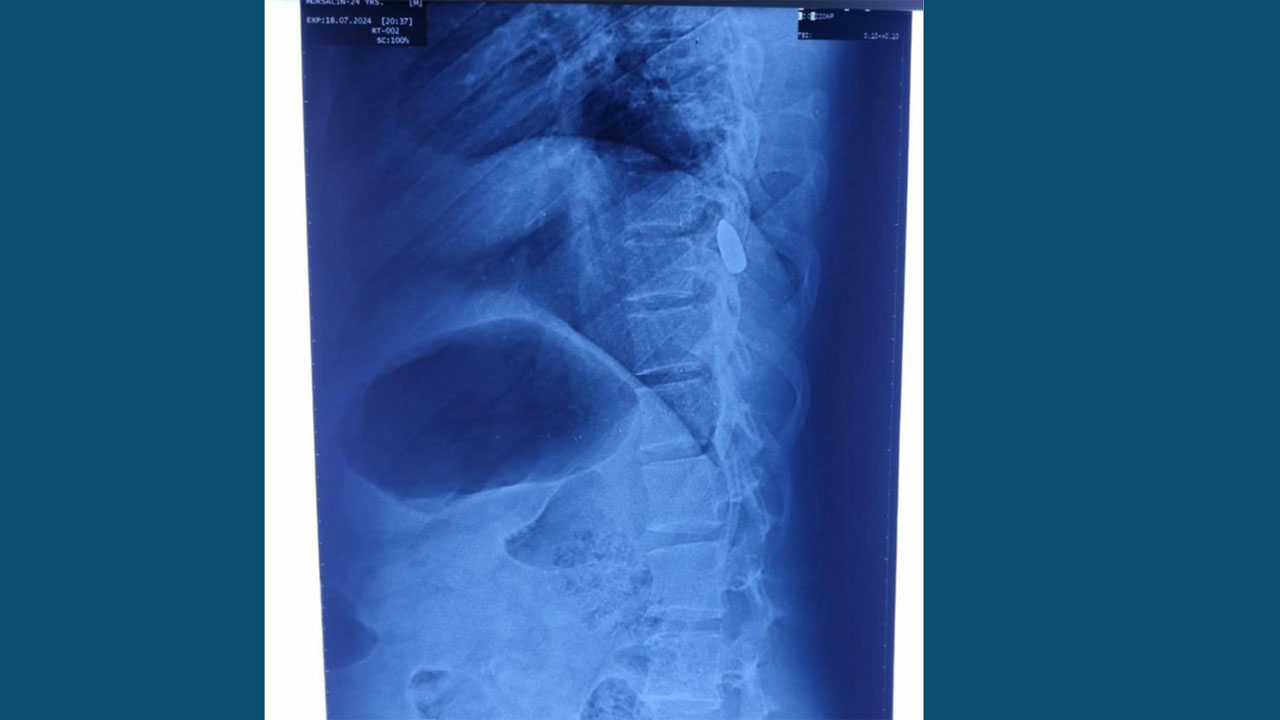

২৬ জুলাইয়ের প্রায় প্রতিটি রোগীই ছিলেন বন্দুকের গুলিতে আহত। তিনি ব্যাখ্যা করে বলেন, “সেখানে ছররা গুলি বা পেলেট ইনজুরি খুবই কম ছিল। প্রায় প্রতিটিই ছিল গানশট ইনজুরি। সেই আঘাতগুলো কোন মাত্রার ছিল তা ভাষায় প্রকাশ করা সম্ভব নয়। আমরা যে বুলেটগুলো রোগীদের শরীর থেকে বের করেছি, তার বেশির ভাগই ছিল লম্বাটে, আবার কিছু ছিল গোল আকৃতির। সেদিন অসংখ্য ‘ব্রট ডেড’ অর্থাৎ হাসপাতালে আনার আগেই মৃত রোগী আমরা পেয়েছি, যাদের প্রত্যেকের মৃত্যুর কারণ ছিল গানশট ইনজুরি।”